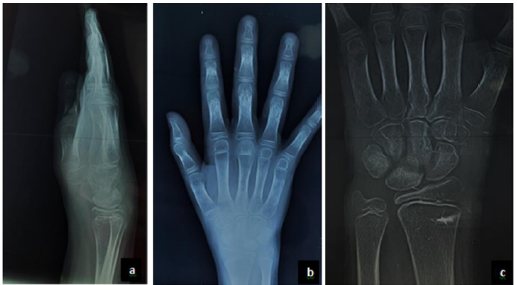

Case Report

Algodystrophy of the Wrist in Adolescent: A Case Report

Nourrelhouda Bahlouli, Fatima Chait, Nazik Allali, Siham El Haddad and Latifa Chat. 12(6): 01-06.